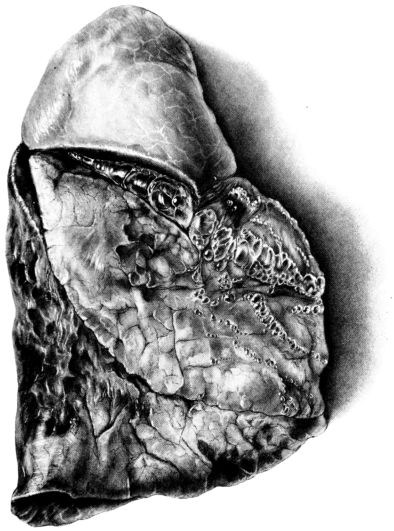

FIG. I. AUTOPSY NO. 99. ACUTE HEMORRHAGIC AND ULCERATIVE LARYNGOTRACHEITIS.

FIG. I. AUTOPSY NO. 99. ACUTE HEMORRHAGIC AND ULCERATIVE LARYNGOTRACHEITIS.